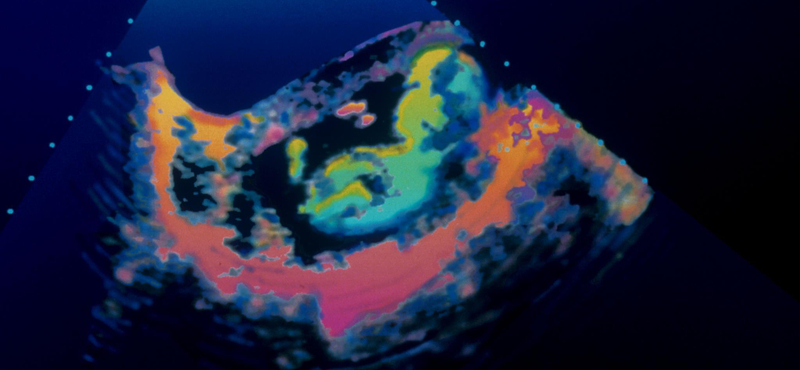

A Borbála nevet viselő, még meg nem született kislánynak azért volt szüksége a beavatkozásra, mert a terhesség 28. hetében kiderült, hogy édesanyja szervezete ellenanyagot termel a vércsoportjával szemben. Ennek következtében a magzatnál komoly vérszegénység lépett fel és záros határidőn belül vért kellett neki biztosítani.

A Semmelweis Egyetem szülészeti klinikájának orvosai három módszer közül választhattak. A leghagyományosabb a koraszülés megindítása lett volna, ami akár igen súlyos kockázatokkal is járhatott volna a babára nézve, ám a szülés eredményes levezetését követően kint már könnyűszerrel lehetett volna neki vért adni.

A másik, Magyarországon sem ismeretlen módszer, hogy a méhlepény és a köldökzsinór találkozásánál adják be a vért és így nincs szükség az idő előtti születésre, ám ebben a speciális esetben ez nem volt járható út, mivel a méhlepény ezúttal nem a méh elülső falán volt, így technikailag nem volt kivitelezhető a beavatkozás.

A harmadik, úttörő módszer a magzat méhen belüli altatását követelte meg és ezt követően lehetett közvetlenül a vénájába juttatni a vért. Az orvosok végül ezt választották és a beavatkozás teljes sikerrel járt, Borbála heteket nyert vele, mely idő alatt akadálytalanul gyarapodhat súlyban is. Azóta a klinikán nyolc hasonló, sikeres beavatkozás történt.